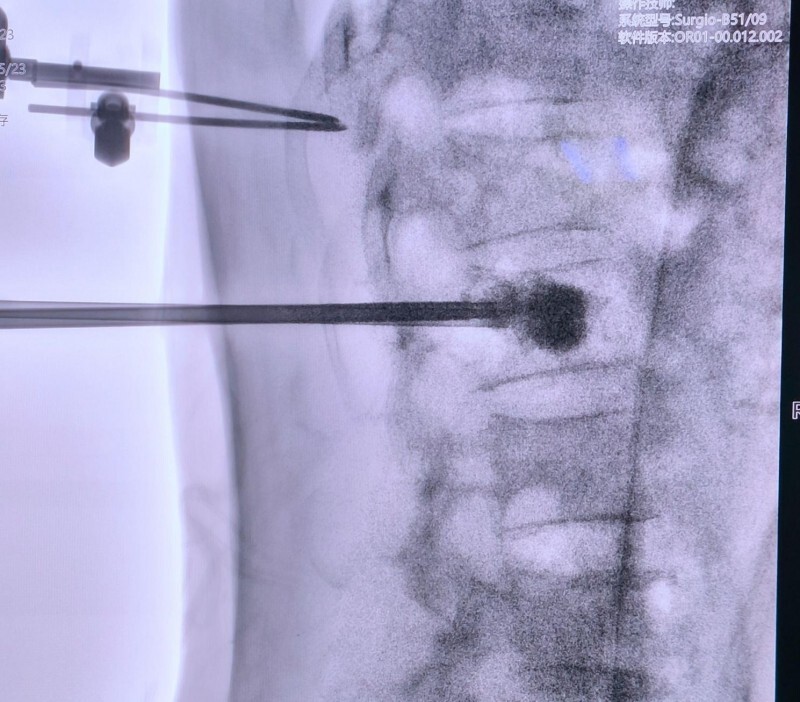

第5例:机器人辅助下腰椎取病理+PKP

第5台机器人手术是天玑机器人辅助下的脊柱手术,该患者前段时间出现腰背部疼痛,休息后无缓解来院检查,发现有“脊柱血管瘤”。看过上周新晨医院关于手术机器人的报道后来院咨询,经过仔细了解后决定请假来做手术。

术中,手术团队通过机器人对瘤体的位置和深度准确定位,很快取到病理组织,并准确地将骨水泥注射到位,手术效果满意,患者术后感觉良好。

术后片子